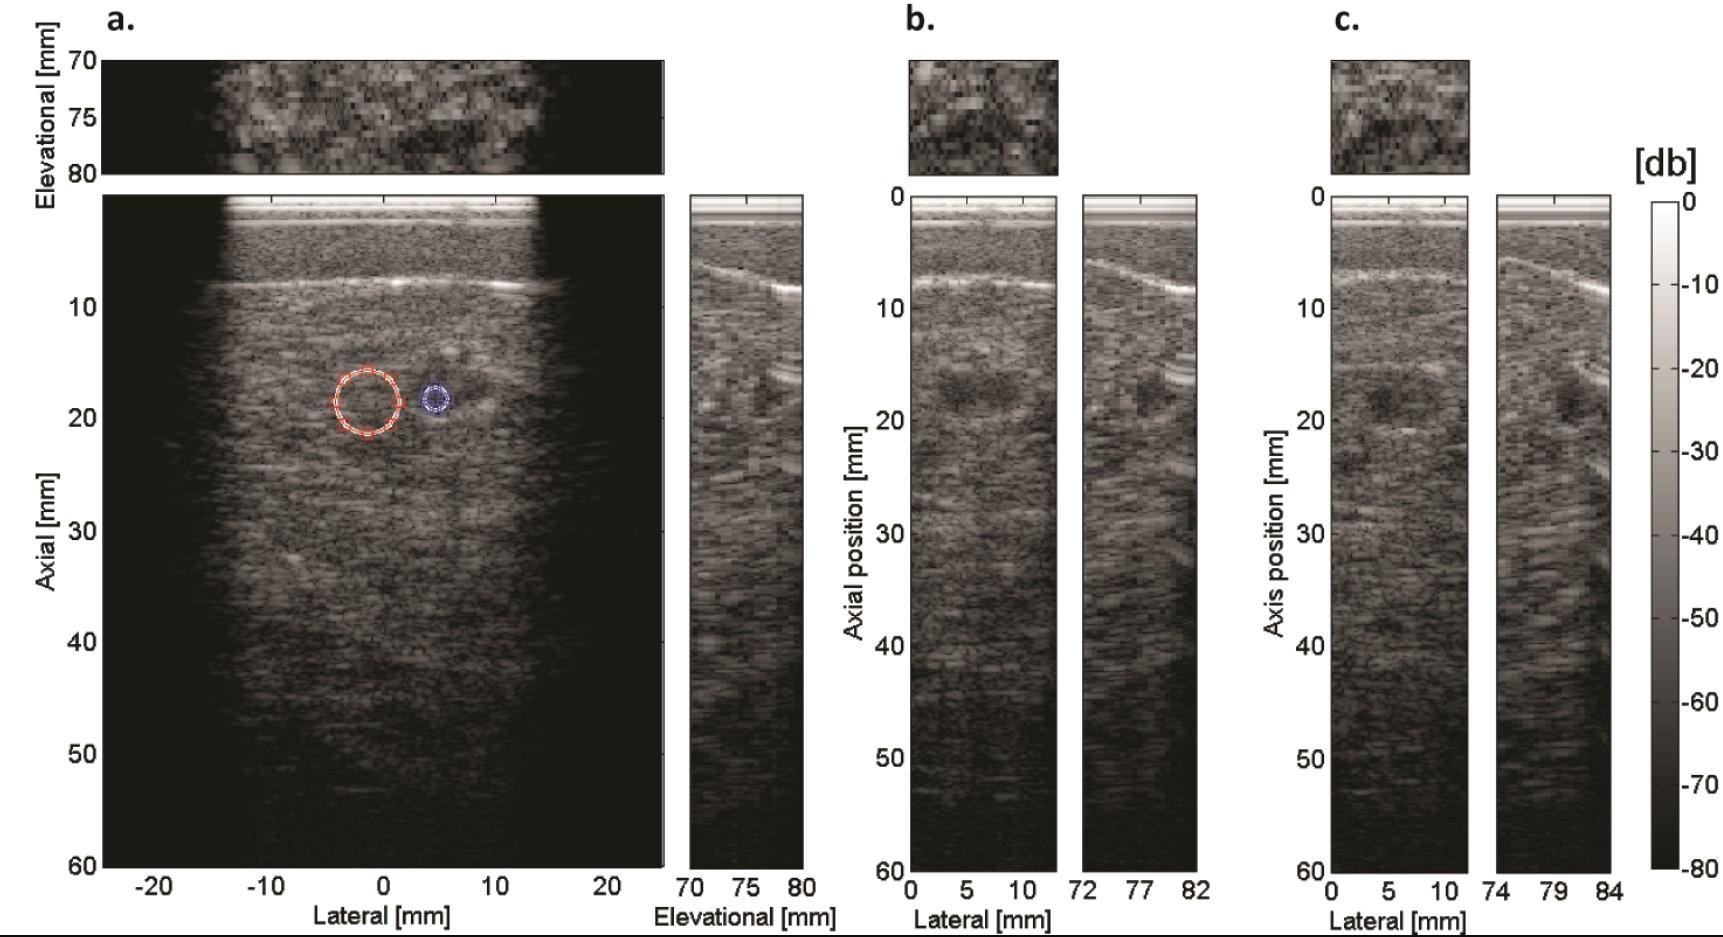

In our studies, we compared the image quality between ultrafast ultrasound (plane-wave) imaging and the currently used conventional focused acquisitions in the ABVS system. Our results suggest that ultrafast imaging will enable breath-hold ABVS examinations, eliminating breathing artifacts while otherwise preserving similar image quality (contrast and resolution). Therefore, 11 steering angles were used in ultrafast imaging resulting in an 18 times increased frame rate. We showed that the frame rate and ABVS transducer moving speed did not significantly affect the image quality (Figure 1). Currently, we are investigating several reconstruction and filtering methods to improve the image quality in ultrafast ultrasound imaging Quantitative Ultrasound.

Coronal (up), transverse (down left) and sagittal (down right) views of a cyst extracted from a 3-D breast phantom volume acquired by moving the transducer by: a) 10 mm/s, b) 20 mm/s and c) 50 mm/s. In the first image CNR measurement positions are indicated (blue: cyst, red: background). In b) and c), only the area around the cyst is shown (Hollander et al., 2016).